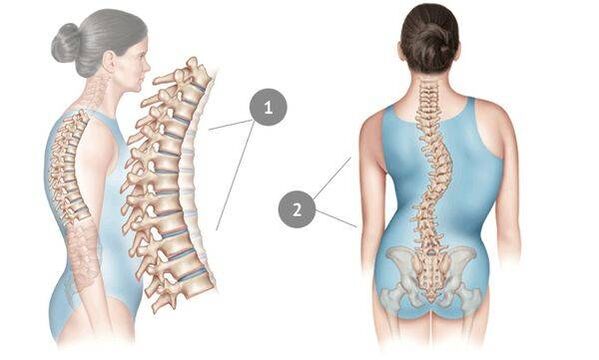

胸部骨软骨病是一种通常在成年后出现且长期不完全显现的疾病。这是由于胸椎自然地受到肋骨的支撑和固定,从而对椎间盘提供了良好的保护。

在这种疾病中,椎间盘的核心变薄并干燥,周围的纤维组织开始恶化,软骨组织发生负面变化。事实证明,脊柱无法应对正常的负荷 - 这主要表现为疼痛的出现,这种疼痛最初表现得很模糊,但随着时间的推移变得越来越强烈。然而,由于巨大的压力——久坐的生活方式、久坐的工作、持续的压力、不良姿势和背部受伤——骨软骨病迟早会影响胸部区域。这种疾病被认为非常常见:三分之一的成年人患有这种疾病。

脊柱骨软骨病晚期表现为脊柱侧凸;有时疾病会扩散到颈椎并导致失声。